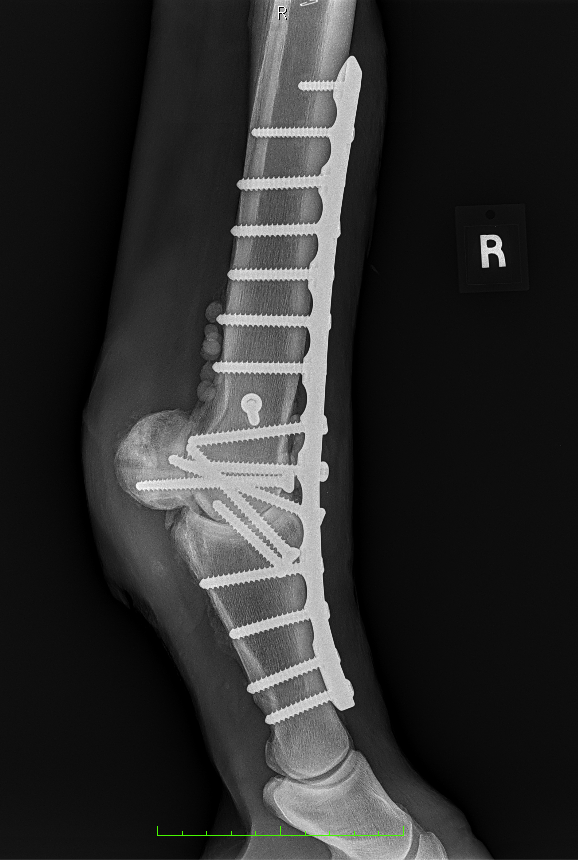

Diagnosis and Procedure: Degenerative arthritis of the fetlock joint, pain leading to overloading the other foot. Fetlock arthrodesis was performed.

Treatment:

Amikacin 250 mg/ml

Daily dose administered: 6 ml

Days of treatment: 5 days

Conclusion: Vetlen Pouch worked well. The surgeon liked the ability to instill the antibiotics onto the plate for 5-days post-op. The mare has done well and is back home.